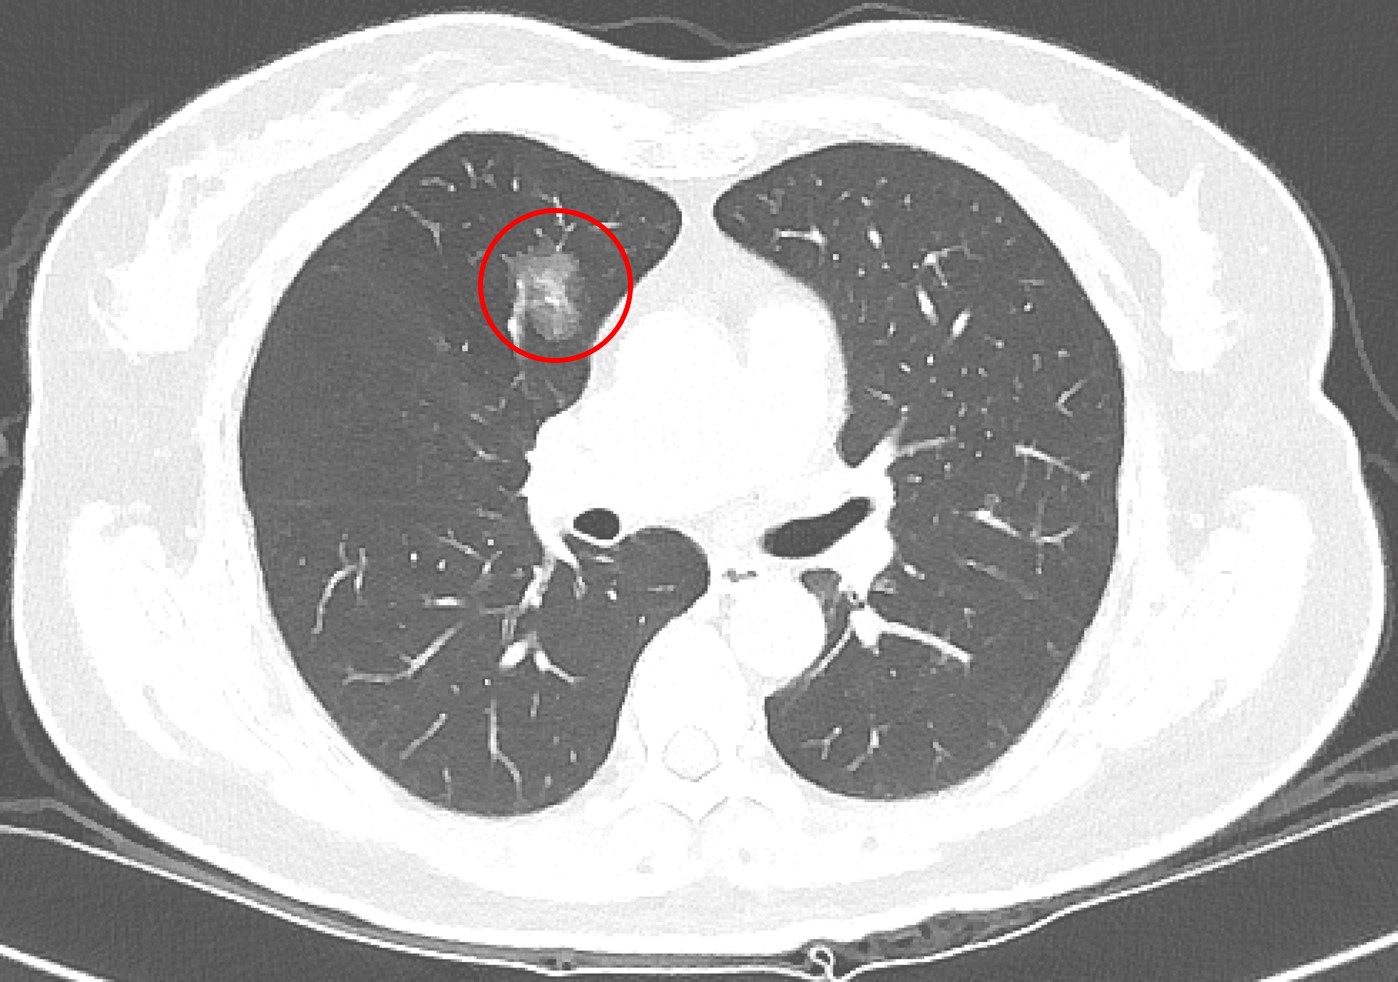

肺癌發生率已居全國第一,影響因子包括抽菸、肺癌家族史及空氣污染等,但吳智偉醫師指出,臨床上超過一半肺癌患者其實不抽菸,因此即使沒有抽菸習慣,也不能完全輕忽風險。近年政府積極推動低劑量電腦斷層篩檢,提升肺癌早期發現及治療的機會,針對肺部小結節,臨床上雖會依據大小、影像型態、生長狀況以及病人的臨床背景進行綜合判斷,但部分良性病灶在影像上與早期肺癌相似,有些早期惡性病灶則生長緩慢、不易立即判別。

有鑑於篩檢發現的小型肺結節在診斷與後續處置上仍有不少挑戰,吳智偉醫師回溯分析台北慈濟醫院2013年至2018年間共6997名LDCT篩檢者資料,並追蹤至2023年,探討篩檢發現之肺腫瘤的生長模式、病理診斷、診斷時程及電腦斷層導引切片的準確性。研究結果顯示,接受手術或切片的腫瘤中,約有三分之二為惡性腫瘤,並以肺腺癌最為常見;而其餘三分之一的良性病理發現則是以纖維化和炭粒沉積最常見。吳智偉醫師說明,纖維化通常是肺部過去曾受感染或發炎後留下的疤痕,炭粒沉積則是空氣中的污染微粒被吸入肺部後堆積形成的結節。這兩類良性病灶之所以難以分辨,在於影像上與早期肺癌相似,因此即使經過多重評估,目前的醫學仍難以僅憑影像,準確區分良性或惡性。此外,約有13%的良性腫瘤,在追蹤的過程中以新發生的病灶(de novo)的形式被發現,讓影像的初期判斷更加艱難。

以許女士為例,沒有抽菸習慣,也沒有肺癌家族史,卻在64歲健康檢查時,從低劑量電腦斷層(LDCT)檢查中發現1.2公分的肺部結節,之後持續在胸腔內科門診追蹤。7年後,許女士71歲時,結節增大至1.4公分,因為擔憂,她與醫師討論後轉至胸腔外科手術,病理結果確診為第一期肺腺癌。由於屬早期肺癌,術後不需化療,追蹤至今恢復良好,無併發症。對此,吳智偉醫師說明,許多肺部結節通常需要追蹤很長的時間,才會有些微變化(一年約長大0.1cm),臨床上會根據變化的型態進一步評斷處置方式。

極早期的結節因為太小,無法經由穿刺切片確認屬性。吳智偉醫師提醒,發現肺結節不必過度恐慌,也不代表一定要立刻動刀,目前國內外的共識是以大小0.8公分作為最基礎的判斷準則,在困難判讀的情況下,建議須定期追蹤。若在追蹤期間出現變大或影像特徵改變,建議與醫師討論或進一步評估手術時機,通常會有機會在零期或第一期及早治療。肺癌若能早期發現,五年存活率超過九成,因此民眾若檢查發現肺結節,應依醫囑規律回診追蹤,才是保護肺部健康的關鍵。